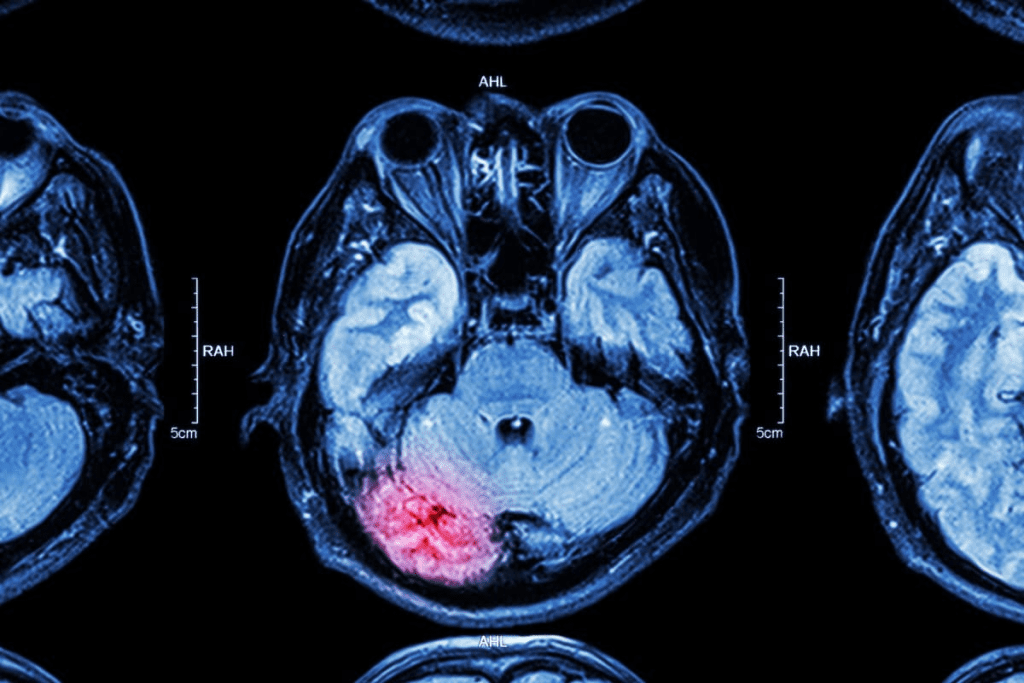

An MRI (Magnetic Resonance Imaging) scan shows detailed images of the body’s inside parts. This includes joints, blood vessels, and organs. Doctors use MRI scans to find out what’s wrong and decide the best treatment.

- MRI scans provide detailed images of internal body structures.

- MRI results are key to diagnosing many health issues.